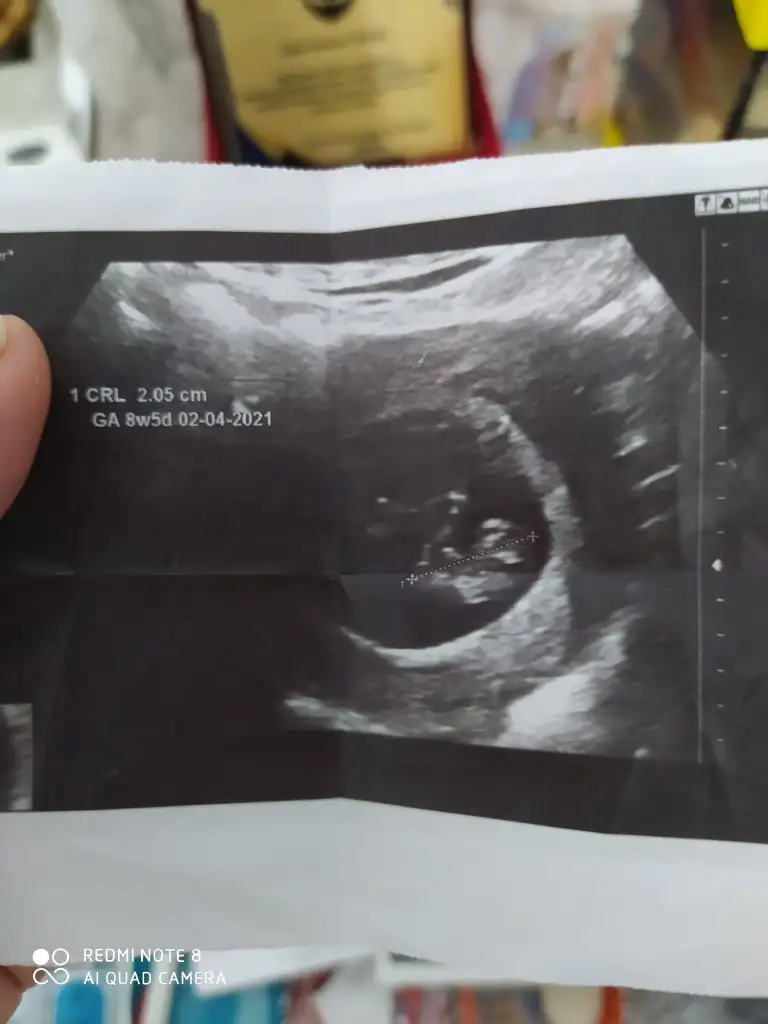

Daha küçükMerhabalar, bu ultrason fotografina gore cinsiyet tahmininiz var midirkalbi 6+4 de 150 atiyordu simdi 9+4 gozuktu bir hafta onden gidiyormus 180 atiyordu. Bir de sag tarafa yerlesmis